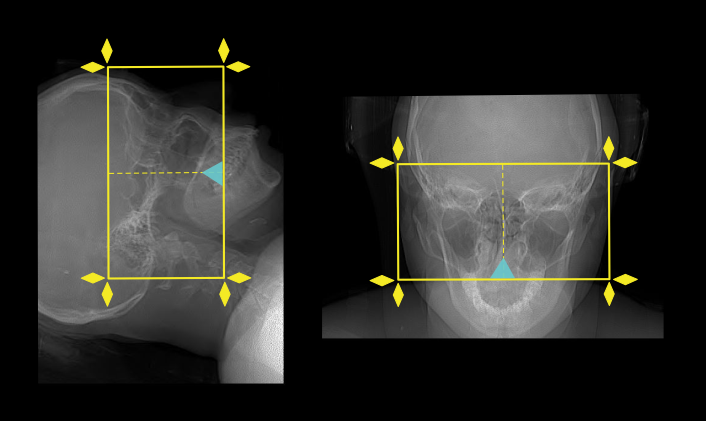

Scan planning

- Plan the scan slab to cover from hard palate up to the superior part of the frontal sinuses.